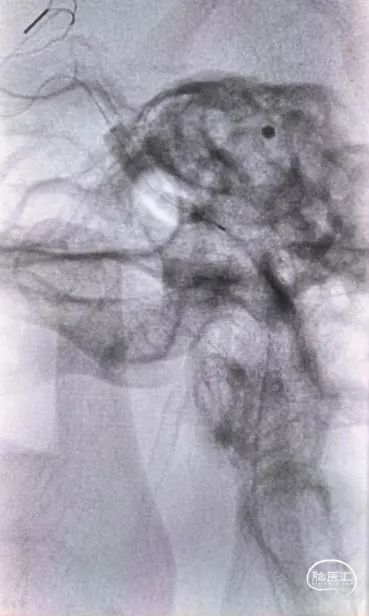

微导丝引导微导管成功通过血管闭塞处至右侧颈内动脉C7段,造影确认真腔。

沿微导管送入6*35mm Syphonet®取栓支架至右侧大脑中动脉M1段并释放。

用2.5*15mm 低压球囊扩张右侧颈内动脉C5-C2段。

扩张后造影示:右侧颈内动脉畅通,可见夹层样改变,C6段仍重度狭窄。

再次用2.0*15mm 冠脉球囊扩张C6段。

依次从远心端到近心端释放4.5*37mm EP支架、4.5*30mm EZ支架、7*40mm 自膨式支架覆盖夹层明显处后造影示:右侧颈内动脉畅通,远端血流mTICI 3级。